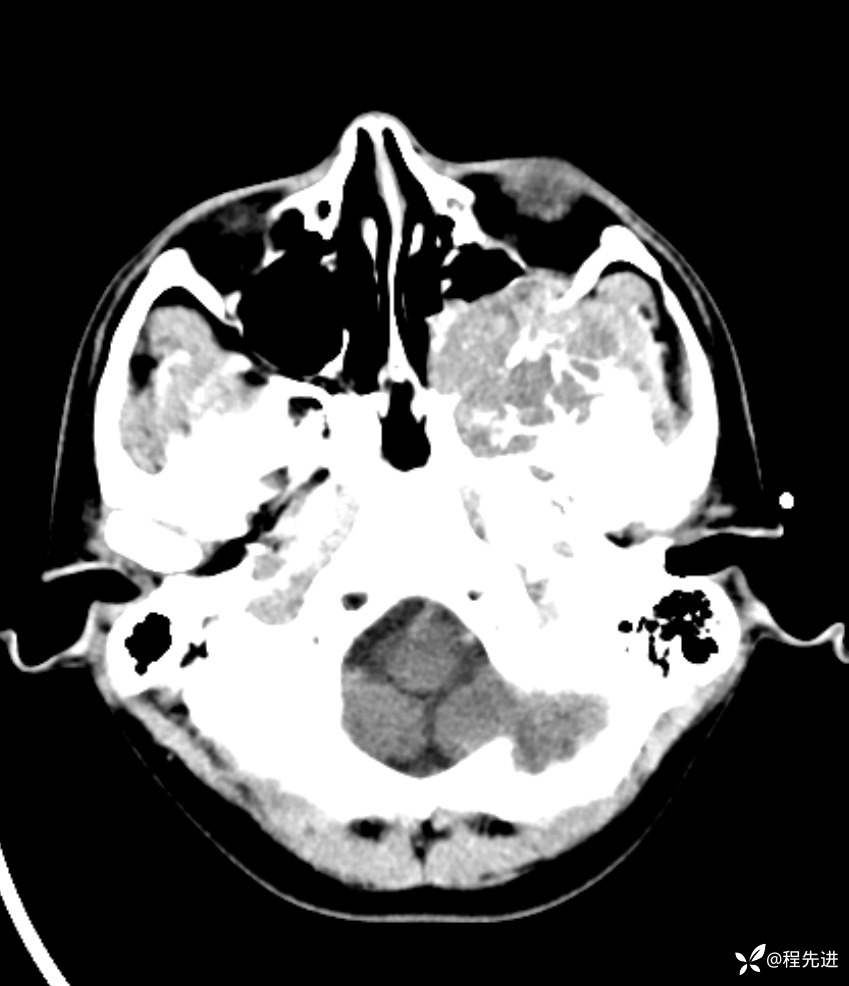

简要病史:左眼视力下降20余天,伴肿胀疼痛不适半月

CT平扫:

脑组织窗: